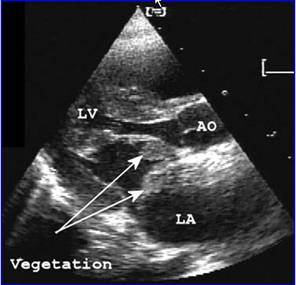

3.晚期並發心血管多種疾病如動脈硬化、心包炎、結腸炎、出血性疾病及神經系統病變。

(1) 長期血透:從20世紀60年代初期就已開始對晚期糖尿病腎病病人套用透析治療,近年來接受血透者有所增加。如1972年還不到0.5%,1981年上升到7.3%,根據1988年美國統計因糖尿病腎病腎功能衰竭接受血透者約為新血透病人的28%。但由於終末期糖尿病腎病除腎臟病變外,幾乎同時都合併有其他器官的血管合併症,特別是由於全身性小動脈硬化,血管壁僵硬,血透的血管通道難以建立,動靜脈瘺管在糖尿病人保留的時間明顯短於非糖尿病人。因此,糖尿病腎病病人血透的存活率,儘管過去10年有了改善,但仍低於非糖尿病人,據Matson與Kjellstrand對369例長期血透病人的隨訪分析,3年累積存活率為45%,5年25%,10年為9%,年齡在60歲以下的1型糖尿病腎病病人血透的存活率20世紀80年代較之60年代有了明顯的提高,1年存活率由60%上升為85%,3年存活率由30%上升為60%,5年存活率由12%上升到45%。但Jacobs等報導歐洲1098例第1年存活率為67%,第2年為49%。1型糖尿病血透病人的死亡率幾乎為非糖尿病人的2.5~3倍,死亡原因仍以心血管合併症為主占51%,其次為中止透析占24%,感染占14%,其他如電解質紊亂(高鉀或低鉀)、高滲性昏迷等約占11%。血透的預後與糖尿病類型有關,1型病人的存活時間明顯短於2型病人,但2型病人有心血管合併症者存活時間短;病人年齡>60歲者預後差,60歲以下則差別不大;至於是否合併有糖尿病視網膜病變對預後關係不大。

糖尿病性腎病糖尿病腎移植病人死亡的主要原因是心、腦血管合併症和感染,特別是在移植後的頭6個月。糖尿病腎移植病人的泌尿系合併症包括輸尿管壞死、膀胱漏尿和神經性膀胱等,遠比非糖尿病人多見,據統計前者為17%,後者僅2.4%。糖尿病尿毒症病人移植前的全身性疾病,特別是腎外血管合併症如心、腦血管病、視網膜病變、糖尿病足等,術前要儘可能地給予治療,否則會影響移植後合併症的發生和死亡。儘管腎移植目前可能是糖尿病尿毒症病人的最佳選擇,但由於供腎來源困難和經濟上的原因,實際只有一小部分糖尿病尿毒症病人可以得到這種治療。因此,對糖尿病腎病最根本的措施,還是儘可能地早期控制好糖尿病以防止糖尿病腎病的發生和發展。